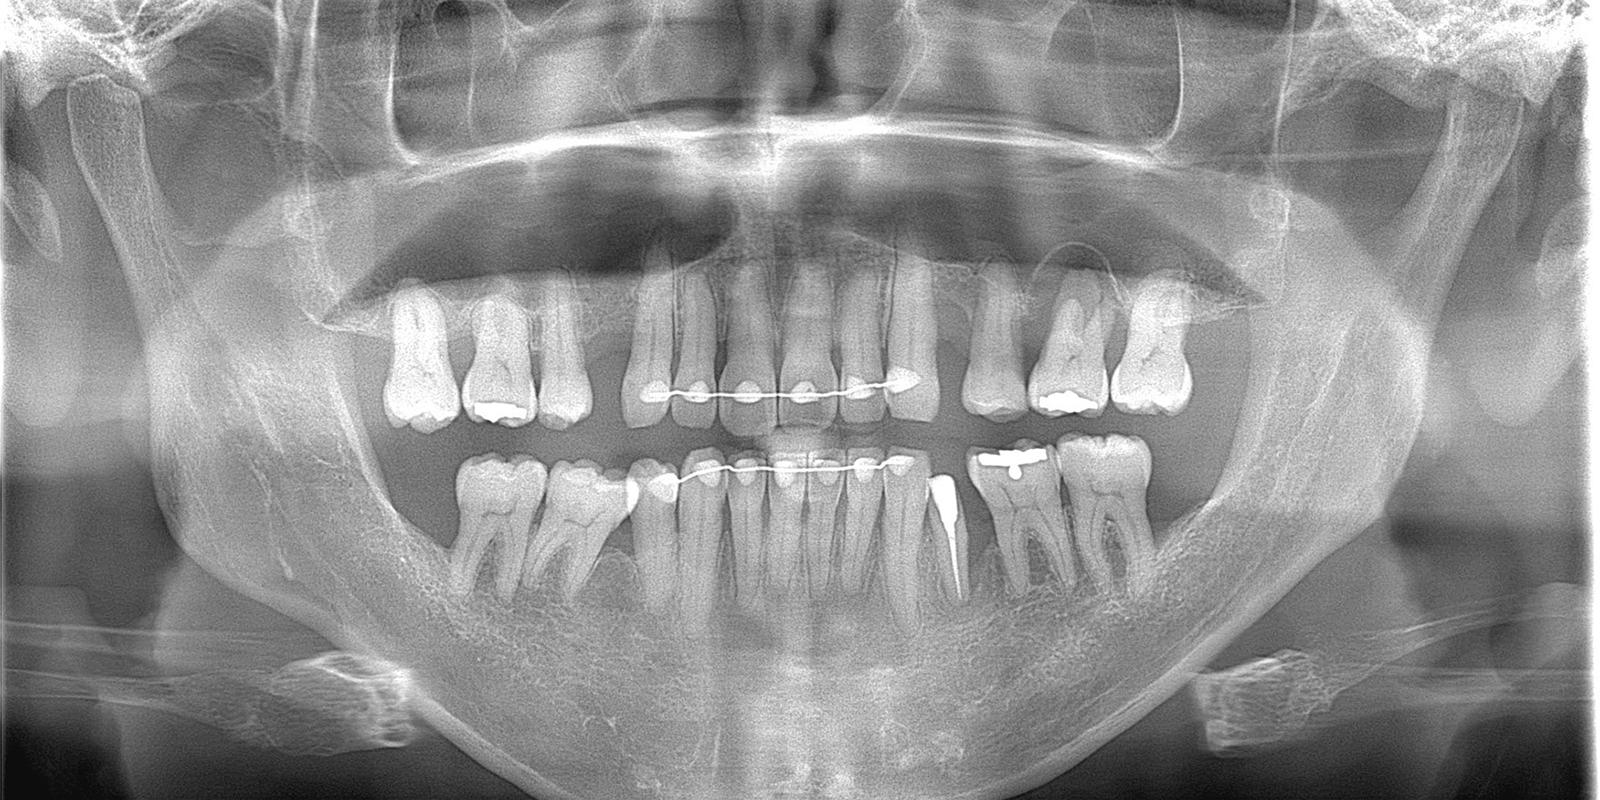

レントゲンでみると右下5番目(実際は左下5)の歯根の先端が黒く抜けています。この状態は、重度歯周病と根尖性歯周炎(根が膿んでる)が混在しており非常に予後が悪いとされています。

術前術後のレントゲンでの比較です。明らかに黒く骨欠損が著しかったところが、白く写り良質な骨が復活しているのがわかります。本症例では、骨補填剤は使っていないため全て自家骨での復活です。上顎両側4番目の歯は今後、インプラント治療を行っていく予定です。